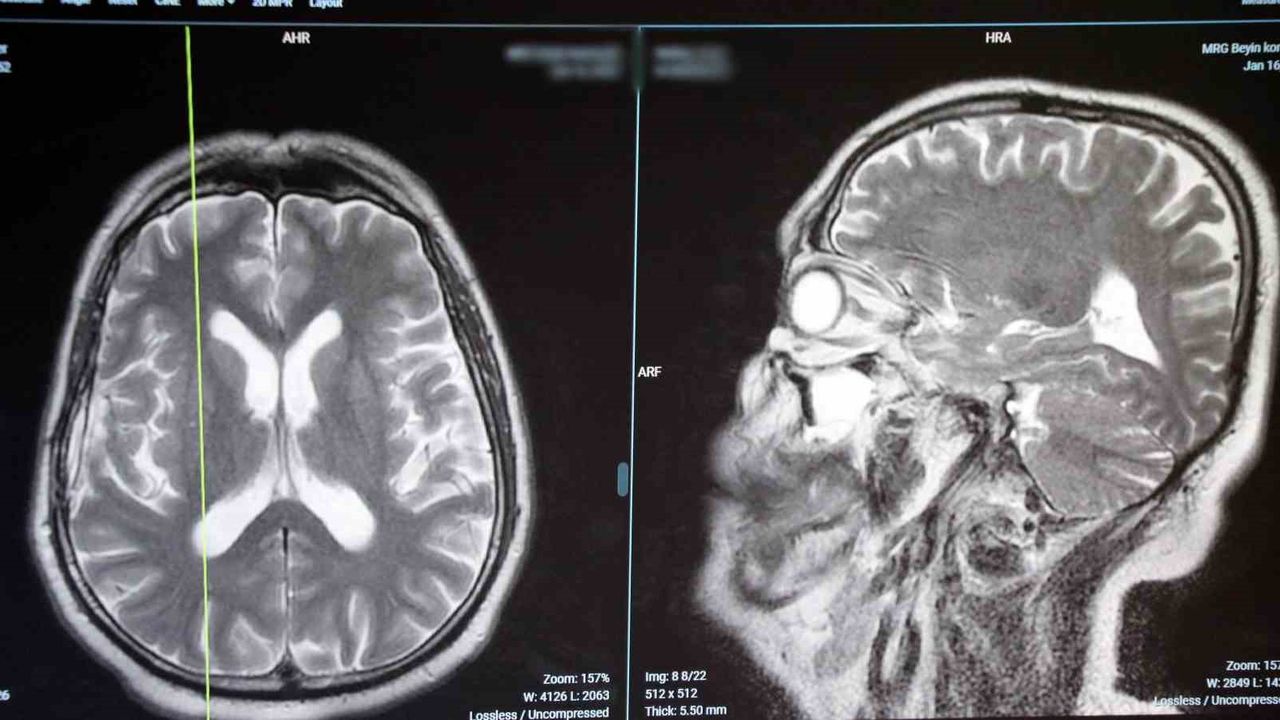

Beyin ve omurga tümörlerinin belirtileri ve tedavi yöntemleri hakkında önemli uyarılarda bulunan Op. Dr. O. Saffet Erk, beyin ve omurga tümörlerinin tedavisinde erken teşhisin hayati öneme sahip olduğunu söyledi. "Tümörlerin erken tanısı, tedavi başarısını artırır ve hastanın yaşam şansını önemli ölçüde yükseltir" diyen Op. Dr. O. Saffet Erk, belirtiler arasında baş ağrısı, denge sorunları, güçsüzlük ve görme bozukluklarına dikkat edilmesi gerektiğini belirtti.

Op. Dr. O. Saffet Erk, özellikle bu belirtileri fark eden kişilerin zaman kaybetmeden uzmanlara başvurmasının önemine vurgu yaptı. Gelişen görüntüleme ve cerrahi teknolojileri sayesinde, erken teşhis edilen tümörlerde tedavi başarı oranlarının arttığını belirten Op. Dr. O. Saffet Erk, "Modern tıbbi yöntemler sayesinde, hastalar daha kısa sürede iyileşip yaşam kalitelerini koruyabiliyor" diye konuştu.